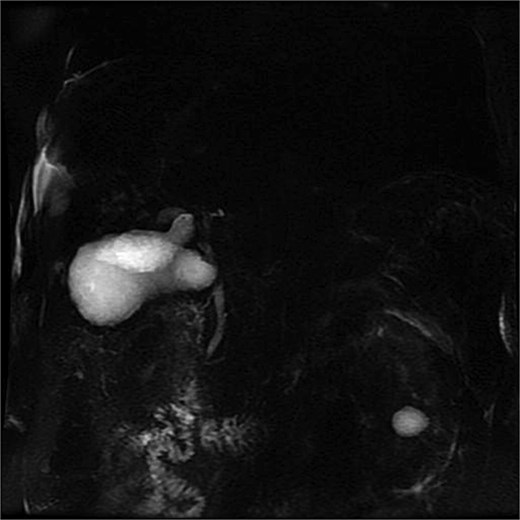

Lab tests showed leukocytosis (15.2 × 103/μl), thrombocytopenia (95.8 × 103/μl), elevated CRP (25.22 mg/dl), procalcitonin (4.49 ng/ml), and total bilirubin (3.5 mg/dl). Liver function was otherwise normal. Ultrasound revealed lithiasic cholecystitis with hydrocholecystosis. Computed tomography (CT) failed to detect duplication (Fig. 1a and b). MRCP confirmed H-type duplicated gallbladder with two independent cystic ducts and mild extrinsic compression of the extrahepatic bile duct (Mirizzi-like pattern) (Figs 2 and 3). MRI sequences (T1 LAVA-Flex and T2 PROPELLER with fat suppression) also demonstrated the duplicated gallbladder and supported the MRCP findings (Fig. 4). No choledocholithiasis was seen.

MRCP (thick-slab 2D coronal oblique) showing duplicated gallbladder (H-type) with two independent cystic ducts and no evidence of choledocholithiasis.